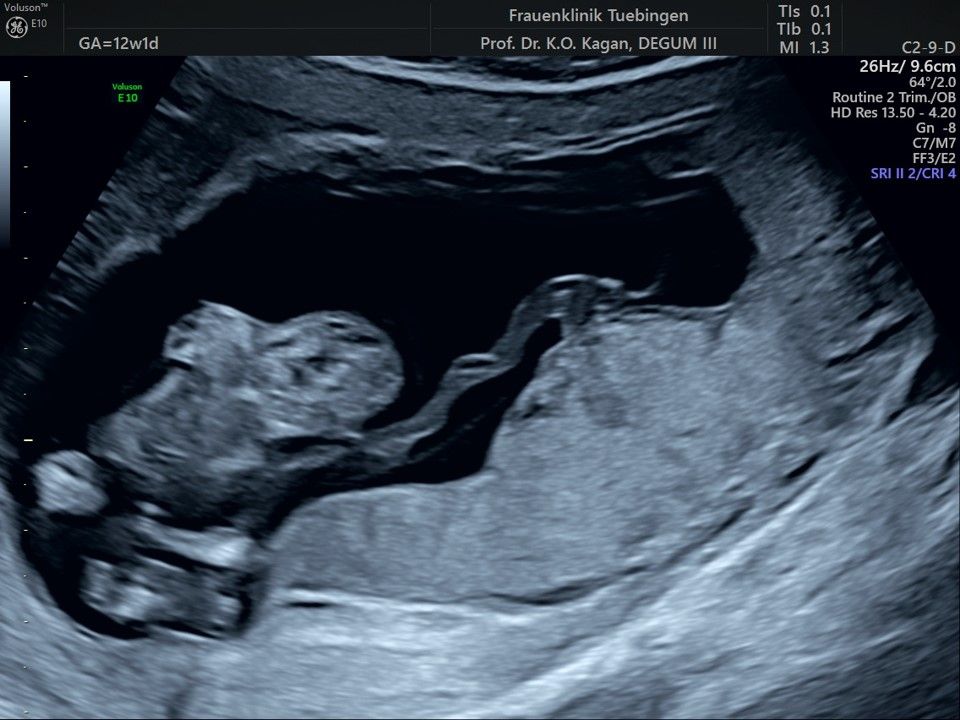

Fetale Anatomie